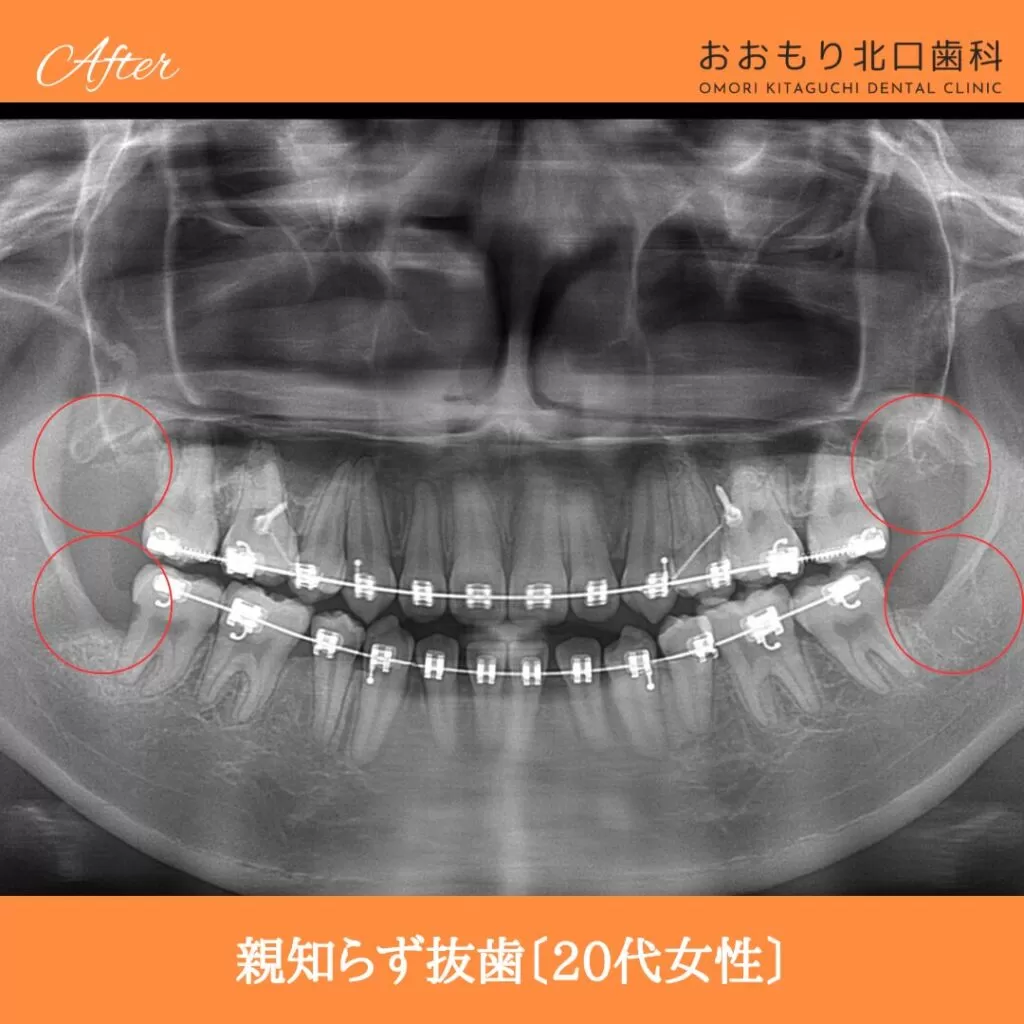

症例紹介㊶親知らず抜歯(20代女性)

本日は「親知らず抜歯」を行われた患者さまのビフォーアフターをご紹介します。

【治療名】親知らず抜歯

【患者さん】20代女性

【リスク】 親知らずの抜歯は、手術中は麻酔により痛みを感じることがほとんどありません。

しかし、麻酔が切れた後には、時には腫れや痛みが発生することがあります。